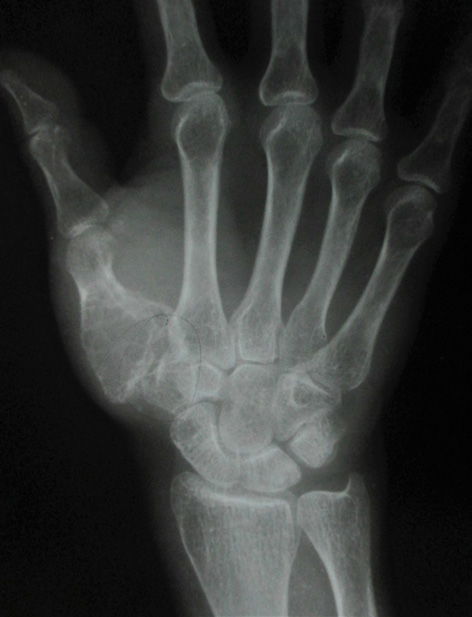

In November 2015 one 60 years lady presented in a newly recognised Medical College of eastern India (Murshidabad Medical College) with recurrence of GCT of the 1st MC of left hand and soft tissue involvement. One year back she was presented in another medical college with intraosseous Capancci grade III lesion of the same site of two years duration where it was treated with narrow margin resection, interposition bone cement on a Kirschner wire (K wire) (Figure 1). It started recurring after 8 months of resection. But presented to us after another one year when extensive extension within soft tissue took place. In plain x ray one small osteolytic lesion was noticed over mid shaft of second metacarpal of the same hand which was not seen in earlier radiographs. MRI was done to identify adjacent bone involvement and to know extent of the lesion in soft tissue (Figure 2). Involvement of regional lymph node and lung metastasis were excluded clinically and radiologically.

Figure 1 a. Initial X-ray initial presentation 3 years back; post-operative X-ray after initial operation; b. immediate; c. subsequent.